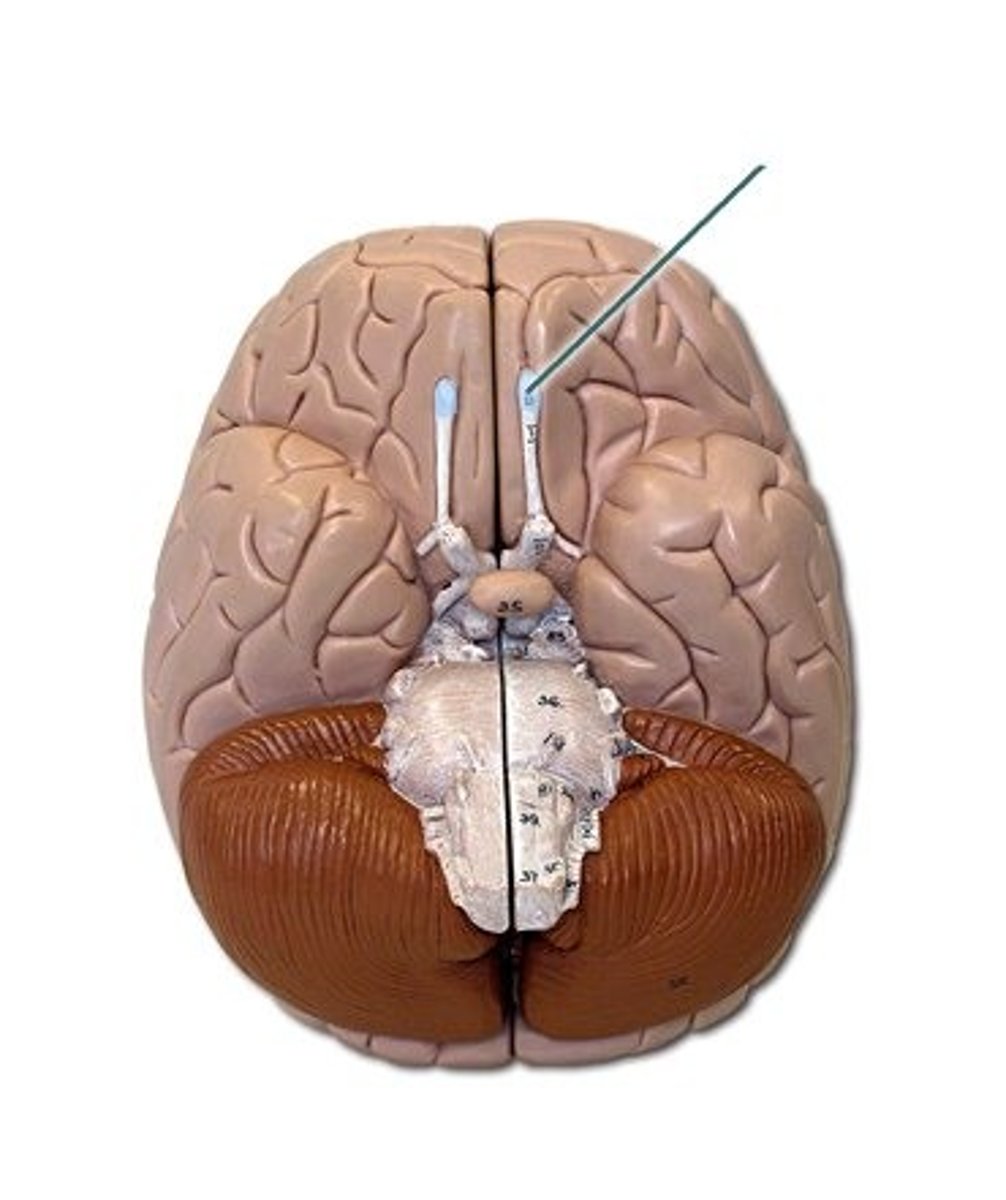

longitudinal fissure